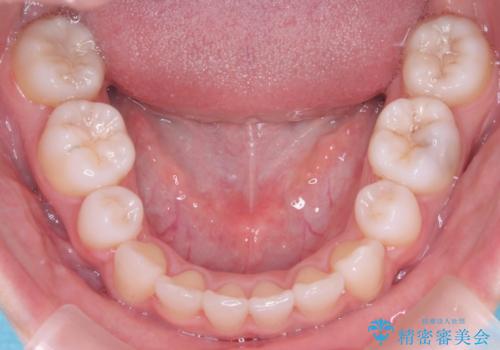

- 左上の犬歯の凸凹や正中のずれを主訴に来院されました。

凸凹を治すために、上下左右の小臼歯を抜歯してワイヤー矯正を行いました。

患者様には、顎間ゴムを使用していただくことで、2年という期間で治療を終了することができました。